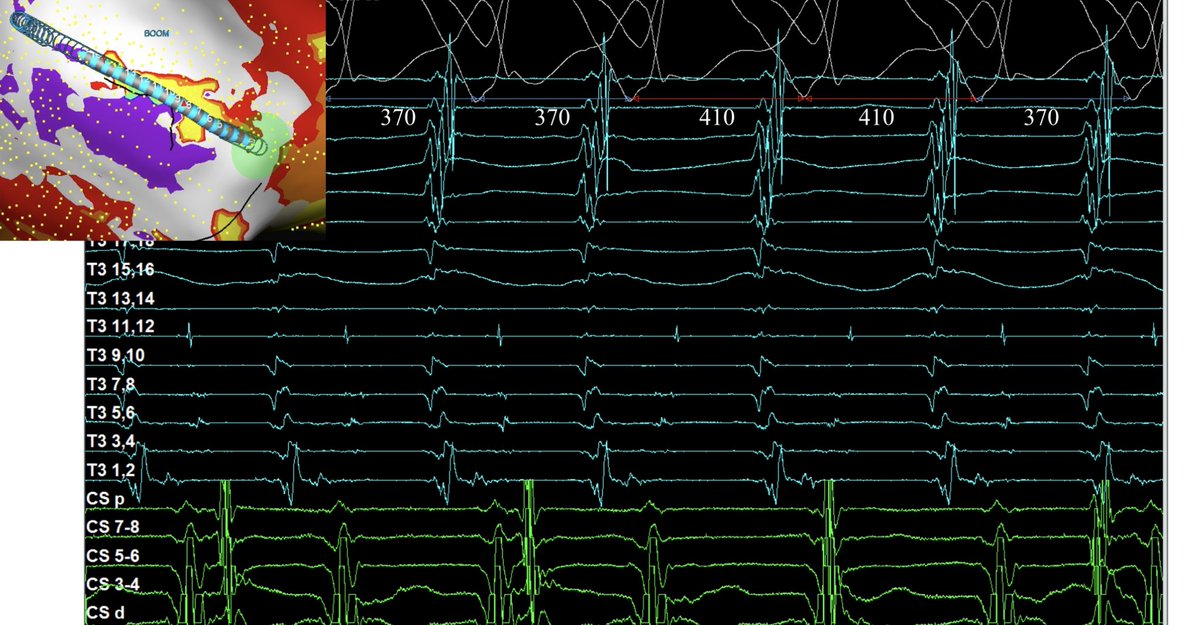

@DrRoderickTung @DrKatrapati @Peteweissmd @su_wilber @MikeZawanehMD Critical isthmus at 11-12 with local EGM stepping out coinciding with TCL jump by 40msec. Suggests circuit has multiple layer components. 12-lead QRS Exit same for both TCL.

Happy Thanksgiving to all! This was a delicious diastolic buffet leading into the holiday with our new tridecapolar catheter in inferoapical scar. 🍗🍽️The intricacies and complexity of this dish are deep..#ablateVT

Great VT week with @BiosenseWebster! #ablateVT Inferoapical isthmus from large Cx infarction. White line is LOB in ILAM, serving as a surface barrier that forces intramural conduction. Need greater resolve of SNO zone, as it is most critical region. Great collaboration ahead!